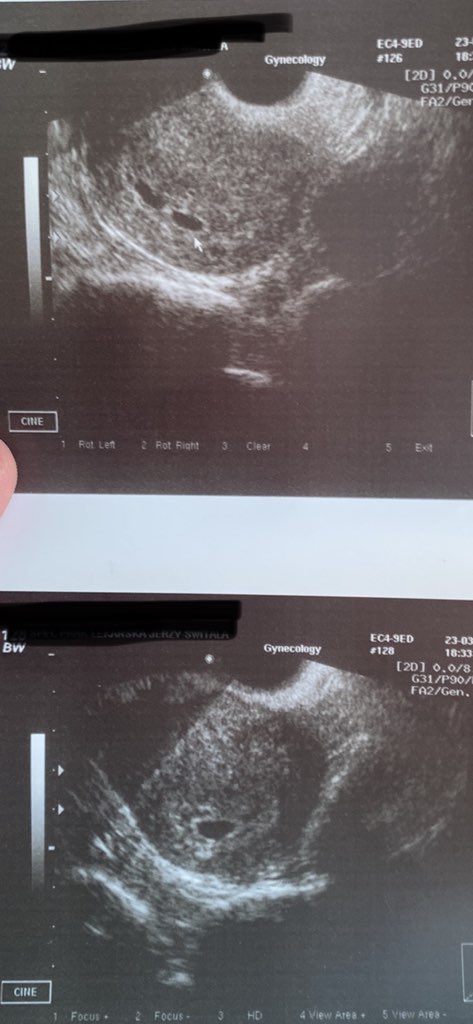

jeśli chodzi o ciąże bliźniacze to ja miałam pierwsze usg 23 marca(zdj z dwoma pęcherzykami) tydz później, bo wariowałam na sama myśl o bliźniakach poszłam na NFZ do ginekologa zrobić usg i był jeden pęcherzyk. Także mam nadzieje ze jest jedno 🙈🤣

• IMG_0185.jpg

IMG_0185.jpg

65,5 KB · Wyświetleń: 86